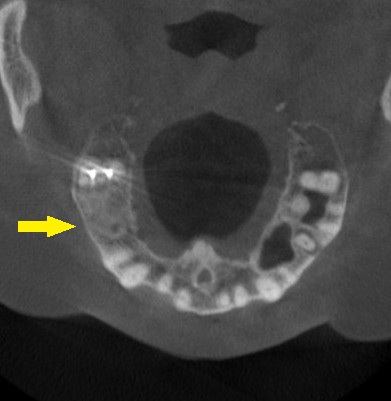

これならと同意いただけましたので、本日、直径6mm、長さ7mmのインプラントを人工骨を用いることなく埋入しました。

下の写真、2段目が手術前、3段目が手術後のCTです。